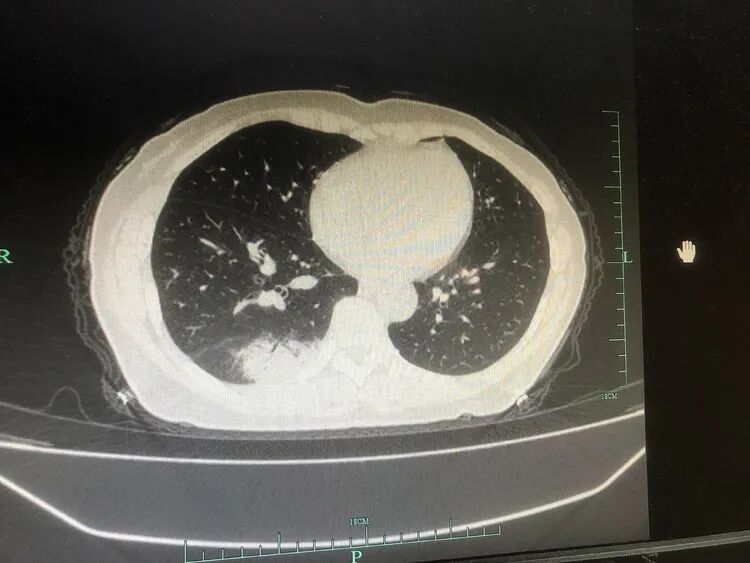

患者,楊某某,中年女性,既往有“風(fēng)濕性關(guān)節(jié)炎”病史,此次因“發(fā)熱、咳嗽2天”于2021-12-12晚入住我科;入院胸部CT提示右肺下葉結(jié)節(jié)影及大片實(shí)變影。

次日患者仍高熱、頭暈乏力,但咳嗽咳痰不明顯,通過(guò)細(xì)讀胸部CT及影像特點(diǎn),陳蒼宋主治醫(yī)師考慮不典型菌感染,再次追問(wèn)病史,了解到患者近期有禽類接觸史,因此,高度懷疑鸚鵡熱衣原體感染,在與呼吸與危重癥醫(yī)學(xué)科主任張君利、副主任陶毅強(qiáng),主治中醫(yī)師賀潔討論后,建議完善相關(guān)檢查,如支氣管鏡檢查等,并于治療上加用莫西沙星覆蓋病原菌。